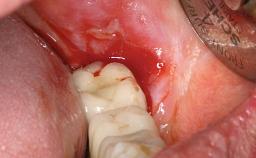

Repeated Acrylic Fractures on a Mandibular Fixed Full-arch Implant-supported Metal/Acrylic Prosthesis

A 77-year-old male patient was referred for the management of frequent and repeated acrylic fracture of his existing mandibular fixed full-arch implant-supported metal/acrylic prosthesis. He also complained about softtissue soreness and the lack of retention and stability of his maxillary removable partial metal/acrylic prosthesis. Both prostheses had been delivered two years previously as part of his full-mouth rehabilitation (caries, tooth wear, tooth fracture). His medical history revealed high blood pressure, controlled with the use of antihypertensive medication.

Periodontal Status History of periodontitis or genetic predisposition